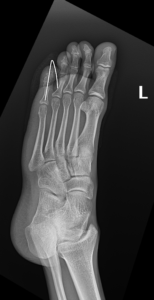

- Foot Fractures.